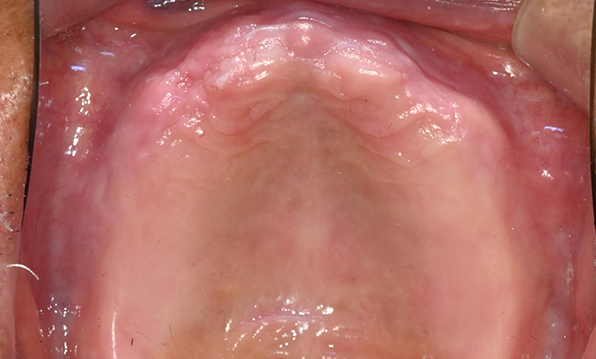

잇몸뼈가 얇은 상태

성공을 위한 노하우, 잇몸뼈 재건 기술

전체 임플란트를 해야하는 환자들은

대부분 고령의 환자들로 오랜 틀니 사용

또는 노화로 인해 치조골이

거의 남아있지 않는 경우가 많습니다.

이 때, 치조골 이식을 병행하여 잇몸뼈 재건 후 안정적인 임플란트 식립을 하고 있습니다.

치료기간 : 2021.04.12~2021.09.15